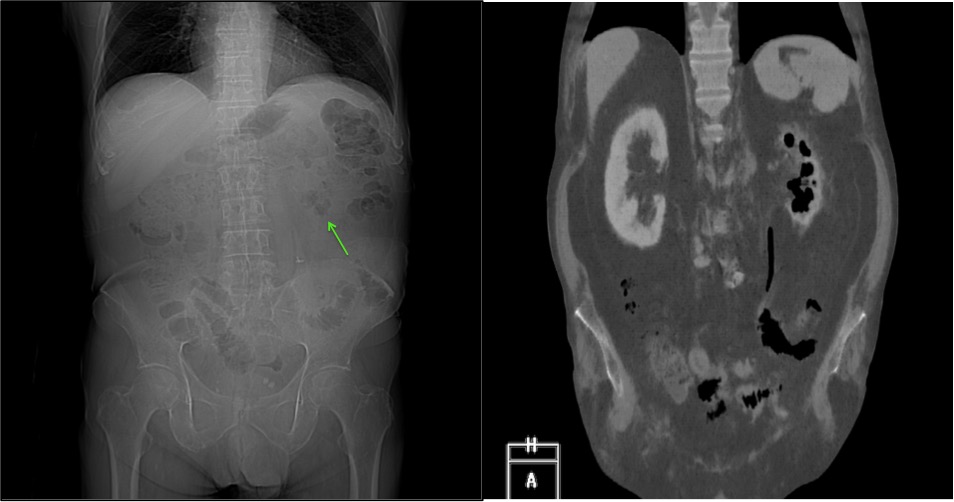

Se procede a realizar TC abdomino-pélvico con contraste en fase nefrográfica y excretora:

Conclusión: se nos presentó un caso de un paciente con una sospecha de infección renal complicada ya que tras cuatro días de tratamiento antibiótico no hubo mejoría. Ante los hallazgos observados en TC, podemos establecer el diagnóstico de pieloureteritis renal izquierda con signos de hidroureteronefrosis leve hasta vejiga.

IZQ: Reconstrucción coronal de TC abdominal donde se confirma el hallazgo en el contexto de una pielonefritis enfisematosa.

B- Con el TCMD con contraste en fase excretora podemos estudiar las vías de manera más prescisa y hacer reconstrucciones. Estudio normal.

C- UIV de una hidroureteronefrosis izquierda leve (grado II/IV) hasta vejiga.